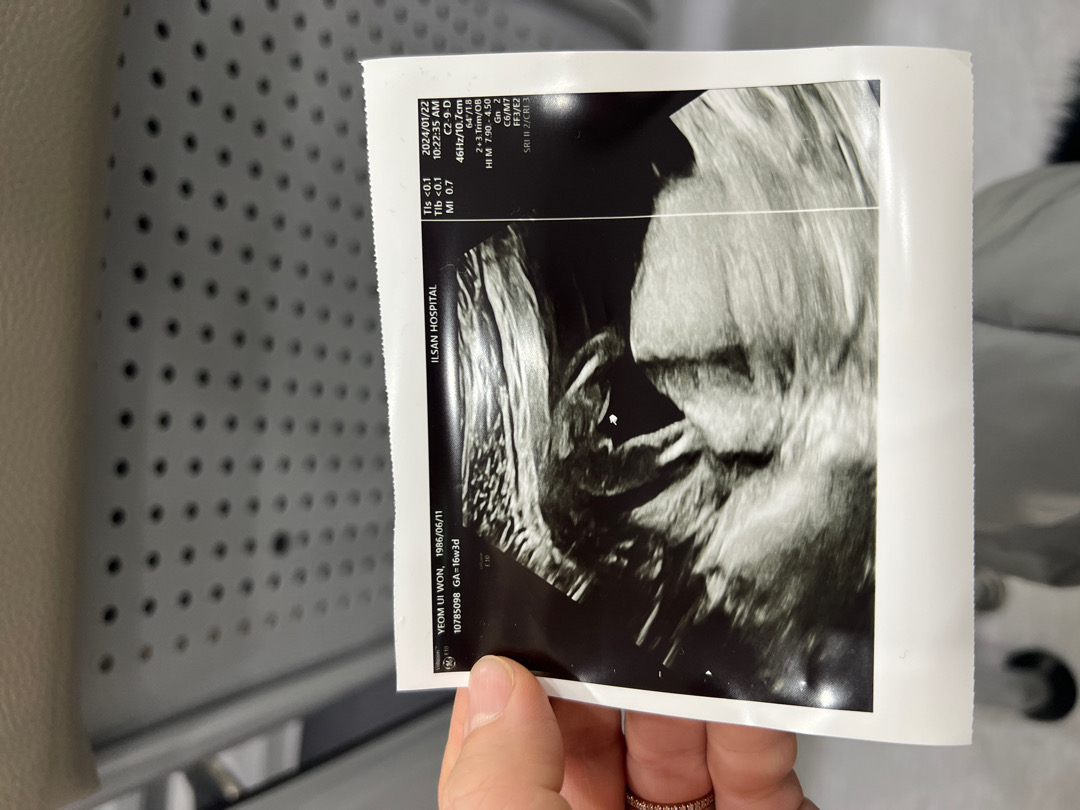

16주 3일 성별보고 2차 기형아 검사했어요

성별 궁금했는데 오늘 드뎌 남편하고 같이 가서 초음파 봤어요!!! ㅎㅎㅎ 저희 부부는 첫째는 딸 원하는데 “엄마 닮았네요”라고 하셔서 남편도 저도 신났어요~ 기형아 검사 특별한 문제 없으면 4주 뒤에 정밀초음파 본다고 하고 그때 다시 한번 성별 봐주신다고는 했어요~ 여러분들 보시기엔 어떠신가요?